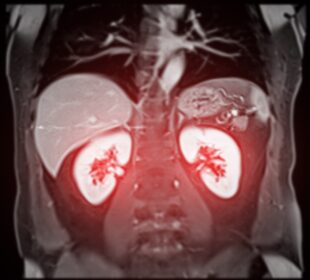

Migrenos sukelti pakitimai smegenų MRT: kaip juos suprasti

Naujausi moksliniai tyrimai rodo, kad migrena neretai pasireiškia tam tikrais smegenų pokyčiais – baltosios medžiagos pažeidimais, kurie matomi atliekant magnetinio rezonanso tyrimą. ...2026 31 kovoAr kalneliai gali sukelti insultą?